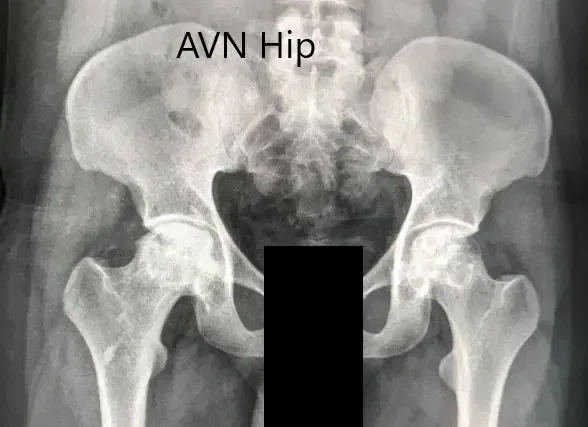

An X-ray was obtained which suggesting bilateral sclerosis of the head of femur and acetabulum changes. There were degenerative changes. An MRI of both hips was obtained.

Preoperative X-ray of the pelvis with both hips in anteroposterior view showing AVN of both hips.